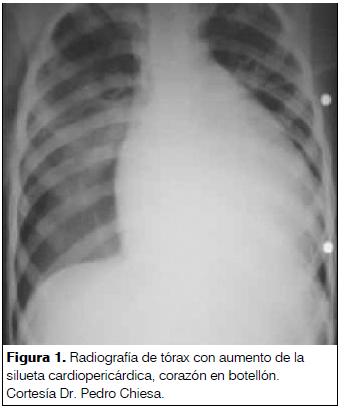

En el ecocardiograma se consideró la presencia de derrame pericárdico cuando la separación de ambas hojas pericárdicas fuera observada durante todo el ciclo cardíaco, confirmando el diagnóstico de pericarditis con derrame. El derrame pericárdico se clasificó en leve, moderado o severo. Se catalogó leve o moderado de acuerdo a lo informado por el ecocardiografista actuante. Se consideró derrame severo todo aquel derrame acompañado de compromiso hemodinámico sin otra causa que lo explique y aquellos que presentaron elementos clínicos o ecocardiográficos sugestivos de taponamiento cardíaco.

Se realizó ecocardiograma en todos los pacientes evidenciando la presencia de derrame en todos los casos. Dos derrames fueron leves, nueve moderados y ocho severos (taponamiento cardíaco).

El ecocardiograma constituyó un recurso fundamental, ya que evidenció la presencia de derrame en todos los pacientes, confirmando el diagnóstico de pericarditis con derrame. Es el método más sensible para el diagnóstico y seguimiento de los pacientes con pericarditis aguda con derrame(6,13,17,19,20).